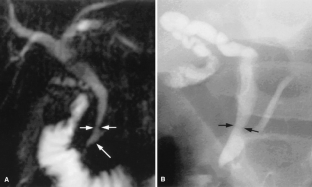

Cholestasis may result from hepatocellular (intrahepatic) disease or biliary tract (extrahepatic) abnormalities. Etiologies causing extrahepatic cholestasis are extremely diverse and invasive procedures, such as endoscopic retrograde cholangiopancreatography (ERCP) and percutaneous transhepatic cholangiography (PTC), were previously required to establish the diagnosis. Due to refinements of magnetic resonance imaging (MRI) techniques, the patient with extrahepatic cholestasis currently can be evaluated noninvasively, and the information revealed frequently exceeds the findings obtained by ERCP and PTC. In this essay, we illustrate the classic MR cholangiographic (MRC) and MRI features of a variety of disorders causing extrahepatic cholestasis, including non-neoplastic disorders of the biliary tract (congenital abnormalities, infectious processes, iatrogenic disorders, and postsurgical complications) and neoplastic conditions (e.g., tumors of the pancreas, biliary tree, liver, ampulla, and regional lymph nodes). In most cases, familiarity with the key MRC features in addition to information obtained via cross-sectional MR images provide sufficient information for adequate lesion characterization.